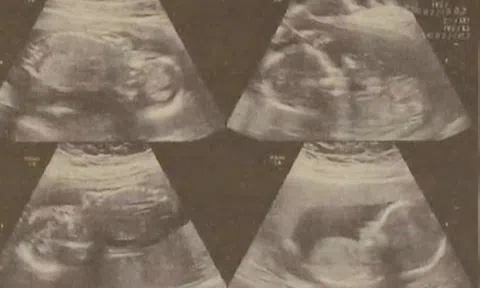

Cô gái sinh 2 con cách nhau 4 ngày, vẫn còn 2 thai nhi trong bụng

Sau khi hạ sinh 2 bé trai cách nhau 4 ngày, sản phụ vẫn còn 2 thai nhi trong bụng. Các bác sĩ đang cố gắng trì hoãn thời gian sinh 2 thai nhi này.

Những nguy cơ sức khỏe của trẻ sinh non

Có rất nhiều yếu tố nguy cơ có thể dẫn tới sinh non như chế độ ăn uống không lành mạnh trong thời kỳ mang thai, không tăng cân trong thai kỳ, tiền sử bệnh tật của mẹ, mẹ bị căng thẳng, trầm cảm, tiểu đường, béo phì, hút thuốc lá, nghiện rượu vv…